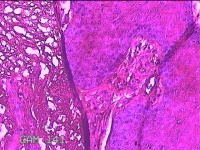

下唇肿物

性别

男

年龄

22岁

临床诊断

口腔黏液腺囊肿

一般病史

下唇肿物一个月余。

标本名称

大体所见

灰白粉红色带皮肤样肿物1x0.3x0.2cm一堆,表面光滑,切开肿物呈实性,切面灰白粉红色,质软。

图1